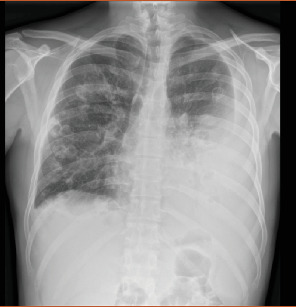

Lemierre综合征(LS)是一种罕见的疾病,估计每年发病率为1-10/1,000,000,定义为口腔和鼻咽感染伴继发性败血症导致脓毒性栓塞和颈内静脉血栓形成的并发症。1936年,在抗生素发明之前,安德烈·勒米尔首次描述了这种综合征。在抗生素出现之前的时代,这是一种常见的疾病,其特征通常是在7-15天内致命,死亡率可高达80%。随着抗生素治疗的发展,LS的发病率迅速下降,如今,它也被称为“被遗忘的疾病”,但死亡率仍然很高(5%),特别是在诊断延迟和治疗不当的情况下。我们提出了一个23岁的病例,他被转介到我们医院,因为咽炎后呼吸困难加剧并伴有高烧,以提高人们对这种严重罕见疾病的认识。如果立即开始适当的治疗,长期的结果通常是好的。肺和血管方面的主要治疗是抗生素治疗,加或不加抗凝和胸管引流。

Lemierre syndrome (LS) is a rare condition with an estimated incidence of 1-10/1,000,000 per year defined as a complication of an oral and nasopharyngeal infection with secondary septicemia leading to septic emboli and internal jugular vein thrombosis. This syndrome was first described by Andre' Lemierre in 1936, before the development of antibiotics. In the preantibiotic era, it was a common condition and it was often characterized by a fatal course within 7-15 days with a mortality rate that could reach up to 80% of cases. After the development of antibiotic therapies, the incidence of LS rapidly declined, and nowadays, it is also known as "the forgotten disease," but the mortality risk remains high (5%) especially in case of diagnostic delay and inappropriate therapies. We presented a case of a 23-year-old who was referred to our hospital for worsening dyspnea associated with high fever following a pharyngitis in order to raise awareness about this severe rare disease. Long-term outcomes are usually good if proper treatment is started with no delay. The mainstays of treatment for the pulmonary and vascular aspects are antibiotic treatment with or without anticoagulation and chest-tube drainage.